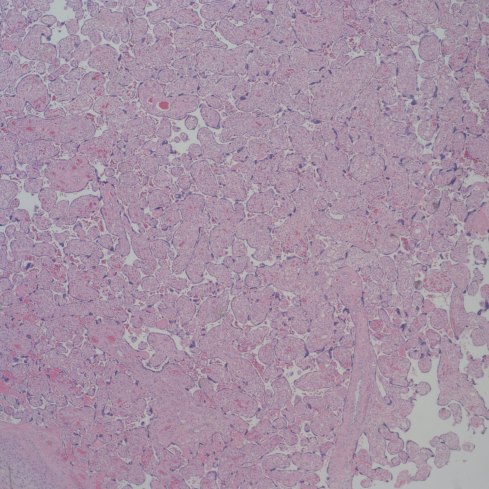

Distinguishing chorangiosis with its large terminal villi from persistent or increased intermediate villi is also not simple. I suspect that this confusion may be responsible for the association of maternal diabetes and chorangiosis. Dr. Ogino and Redline’s paper specifically mentions that the association is also with placentomegaly and delayed villous maturation. This problem can be seen clearly in looking at very early gestation placentas. (fig 2)